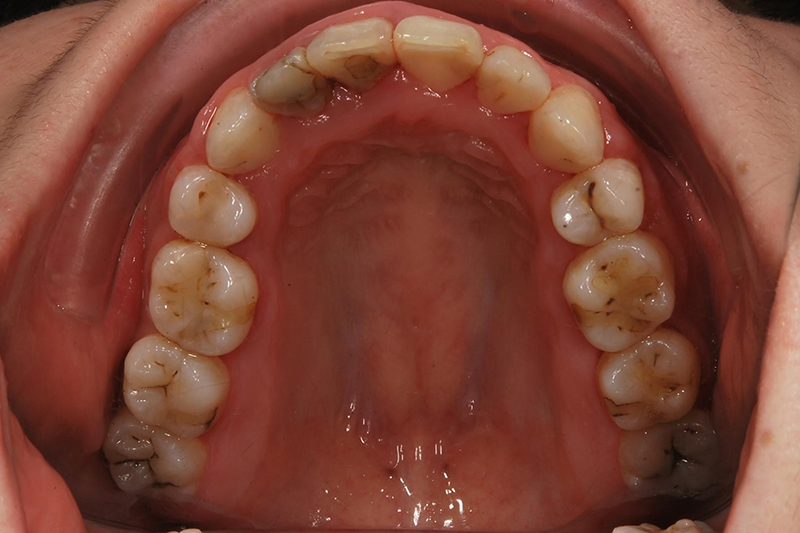

齒列不整

矯正後